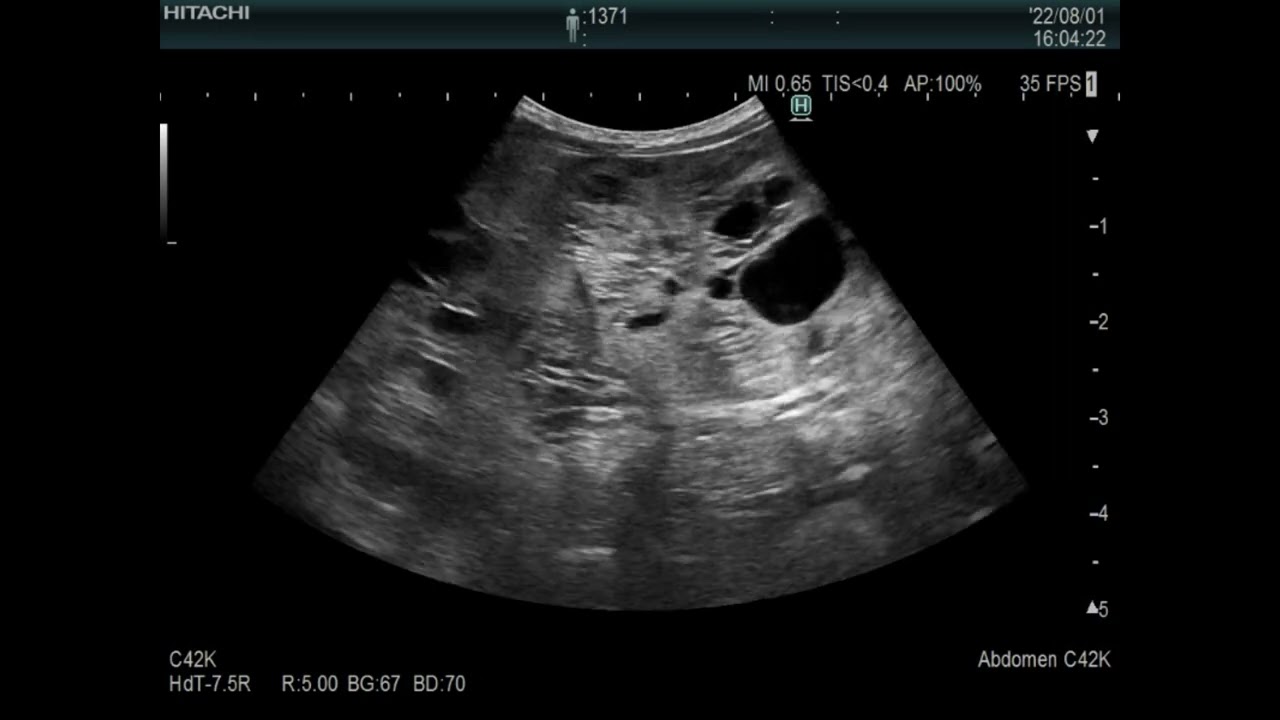

Echo image of Splenic tumor(hemaangiosarcoma) in a dog 犬の脾臓の血管肉腫のエコー